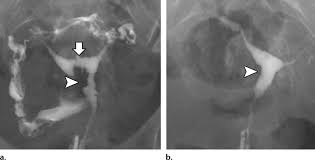

روش دیگر هيستروسالپنگوگرام یا عکس رنگی رحم (HSG) است که به بررسی رحم و لوله های فالوپ می پردازد. در این روش ماده مخصوص در رحم تزریق می شود تا در صورت وجود مشکل در حفره رحم, رشد یا انسداد لوله های فالوپ توسط اشعه ایکس مشخص شود.